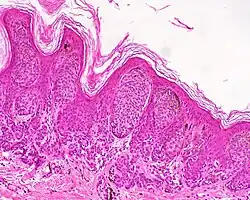

| Compound nevus | Both the epidermis and dermis.[17] |

|

ICD10: D22 (ILDS D22.L14) ICDO: 8760/0 | |